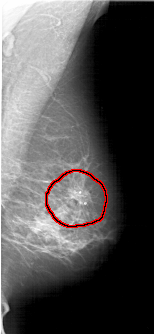

A_1424_1.LEFT_MLO

LEFT_MLO LINES 6871 PIXELS_PER_LINE 2986 BITS_PER_PIXEL 12 RESOLUTION 43.5 NON_OVERLAY

FILE: A_1424_1.RIGHT_MLO.OVERLAY

TOTAL_ABNORMALITIES 1

ABNORMALITY 1

LESION_TYPE MASS SHAPE IRREGULAR MARGINS SPICULATED

ASSESSMENT 5

SUBTLETY 3

PATHOLOGY BENIGN

TOTAL_OUTLINES 1

BOUNDARY